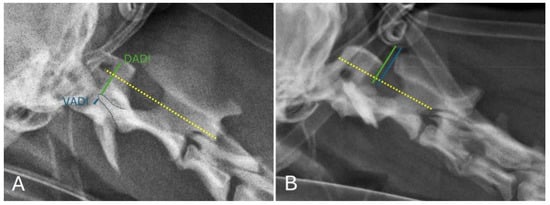

To achieve proper alignment of the atlantoaxial joint and to protect the spinal cord during the procedure, two 1.5 mm or 2.0 mm self-tapping cortical bone screws were inserted into both the C1 and C2 bodies. Predrilling with a drill bit and guide was performed prior to screw insertion. A stop band was placed on the drill bit to ensure adequate predrilling depth. The screws were then inserted through the predrilled hole (Figure 2).

Figure 2. Predrilling with a 1.5 mm drill bit with guide: the blue band was positioned to ensure efficient locking based on the bone corridors and the selected screw size (A); screw insertion through the predrilled hole of a 2.0 mm self-tapping cortical locking screw (B).